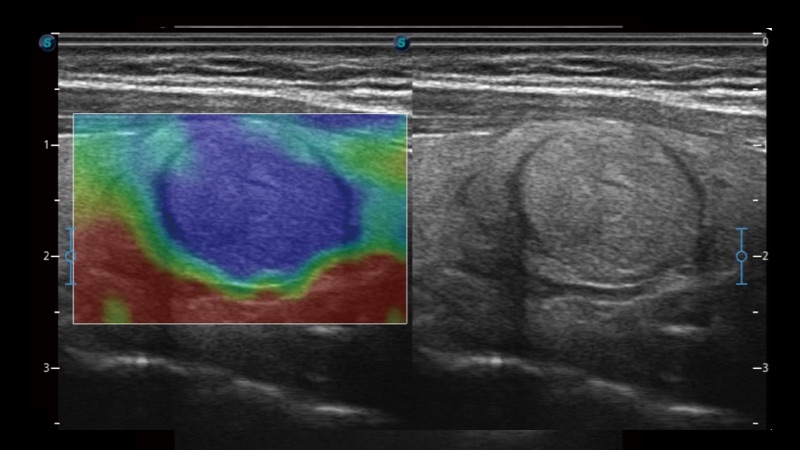

凭借开立医疗先进的成像技术和优异的探头技术提供的清晰的图像表现,您可以更自信地做出临床决策。